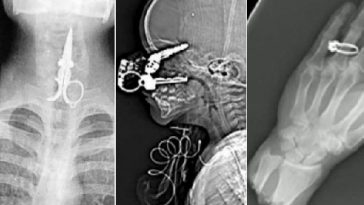

8. Tady někdo vdechl sponku.

9. Takto vypadá předkus.

11. Kroužek v nose.

my nose ring in this jaw x-ray